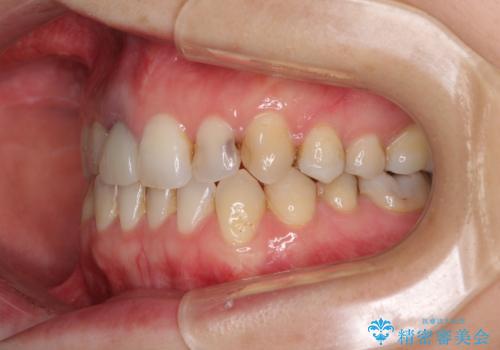

前歯のクロスバイトと治療が必要なむし歯 矯正とセラミックの総合歯科治療

- 前歯が痛いとのことで来院された患者様です。

前歯は根管治療が必要であったため、まずは根管治療を行いましたが、痛みが引いた後、矯正治療や前々から治療が必要と言われてきた歯を治療したいとのことでした。

前歯のクロスバイトはインビザラインで改善し、抜歯が必要な部分はインプラントを、その他むし歯が進行している歯はセラミッククラウンによる補綴治療することとしました。

磨きにくく、何度もむし歯治療を繰り返していた前歯をスッキリと整えることができました。